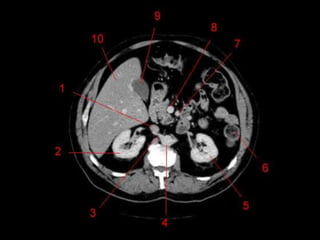

Subdivisão Funcional • Osoito segmentos são divididos: – A primeira divisão é realizada dividindo através da Porta Hepática, em esquerdo (I a IV) e direito (V a VIII) – A divisão é feita baseada em um relógio – Caudado é o segmento I – No ‘lobo’ esquerdo, o IV separa-se do II e do III pela veia hepática esquerda, representado anatomicamente pelo ligamento falciforme. – II e III se dividem através de uma linha imaginária transversal na altura da porta hepática. – No ‘lobo’ direito, se divide os segmentos através de uma linha transversal e pela veia hepática direita.

Subdivisão Funcional • Fundamentalimportância para Ressecção. • Maioria das lesões são do fígado direito.

Vasos Hepáticos • Veiaporta – Formada pela união da Veia Esplênica e Mesentérica Superior • Artéria Hepática – Segmento da Tronco Celíaco – Dividida em Comum e Própria pelo surgimento da artéria gastroduodenal. • Na maioria das pessoas, a artéria é anterior a veia (91%). Na maioria das pessoas, a artéria hepática direita passa atrás do ducto hepático comum. (64%)

Técnicas de Imagem •US: Primeiro exame pedido ao: 1) dor no hipocondrio direito; 2) testes de função hepáticas anormais; 3) suspeita de malignidade. • TC: Tres fases – Arterial (10 a 20 segundos) – Fase venosa portal ( 30 segundos ) – Fase venosa hepática (60 segundos) • TC Portografia: Metastases.